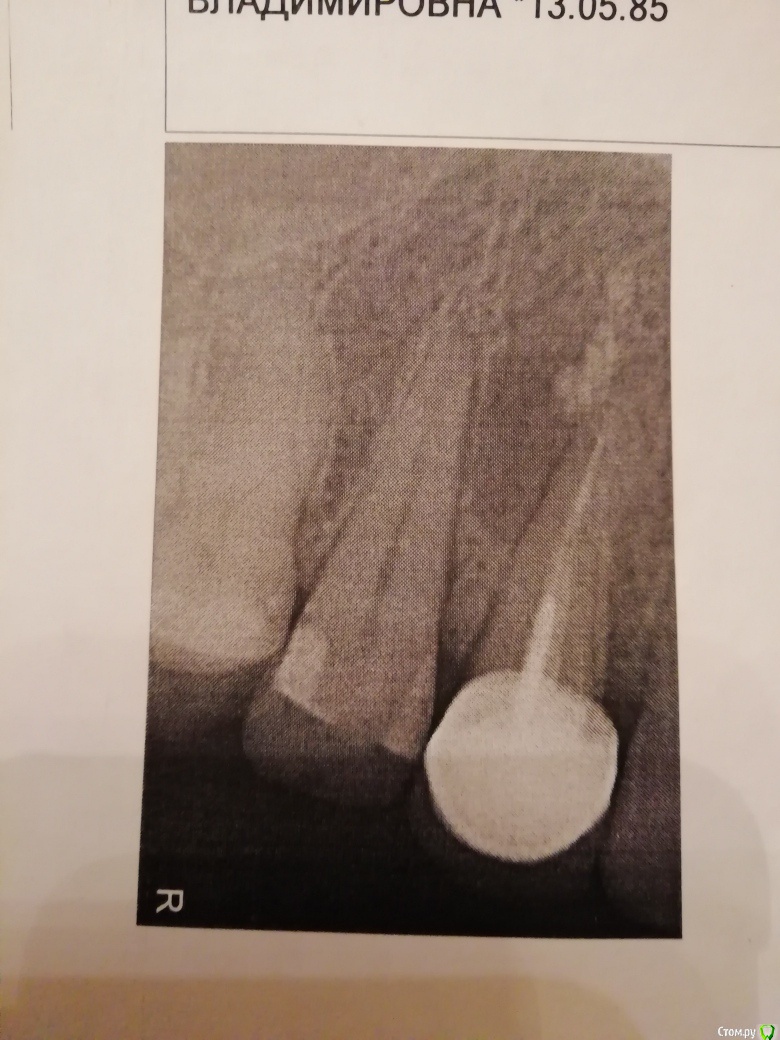

elistac21 Опубликовано 9 января, 2020 Автор Поделиться Опубликовано 9 января, 2020 В продолжение темы. Была сегодня у ортопеда, который мне ставил коронку, по поводу ее снятия для дальнейшего лечения кисты. Сделал еще снимок и сказал, что каналы не перелечить и зуб нужно удалять. Скажите, по снимкам, у зуба нет шансов? Снимки - 3 января в одной клинике, куда обратилась с болью и флюсом, и в другой клинике старый 2010 г (без коронки) и сегодня, 9 января. Ссылка на комментарий